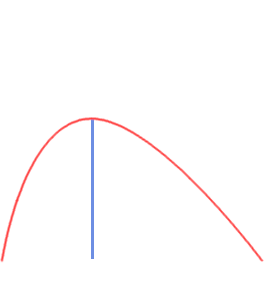

Multi Echo (ME-fMRI)

- Single Echo (SE): during fMRI acquisition we collect the signal once per TR at a certain TE to obtain one timeseries per voxel

-

Multi Echo (ME): we collect the signal multiple times at different TEs to obtain n timeseries per voxel

TR

BOLD [a.u.]

Multi Echo (ME-fMRI)

- Single Echo (SE): during fMRI acquisition we collect the signal once per TR at a certain TE to obtain one timeseries per voxel

-

Multi Echo (ME): we collect the signal multiple times at different TEs to obtain n timeseries per voxel

TR

BOLD [a.u.]

Optimal combination

For each voxel and TR, we can Optimally Combine the echo volumes with a weighted sum based on their contribution to \( T_2^{\star} \)

In this way, spatial CNR and tSNR are maximised and the signal can be recovered in areas of drop-out

Posse et al. 1999 (Magn Reson Med)